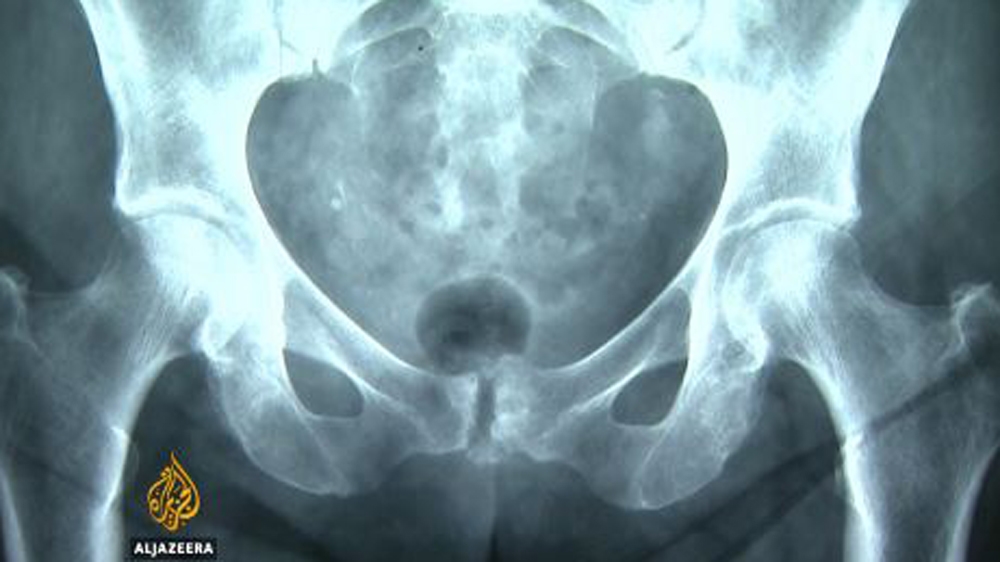

The procedure is called symphysiotomy: The symphys part refers to the pelvis, the “otomy” meaning separation.

Historically, symphysiotomy was only ever used as a last resort by surgeons if they had no way of getting a baby out of a pregnant woman.

Sawing open a woman’s pelvic bone to release a baby in the wrong position isn’t something any doctor would do on purpose.

The side effects, the catastrophic impact of breaking the pelvis, the purpose of which is to hold a body in place, were apparently ignored.